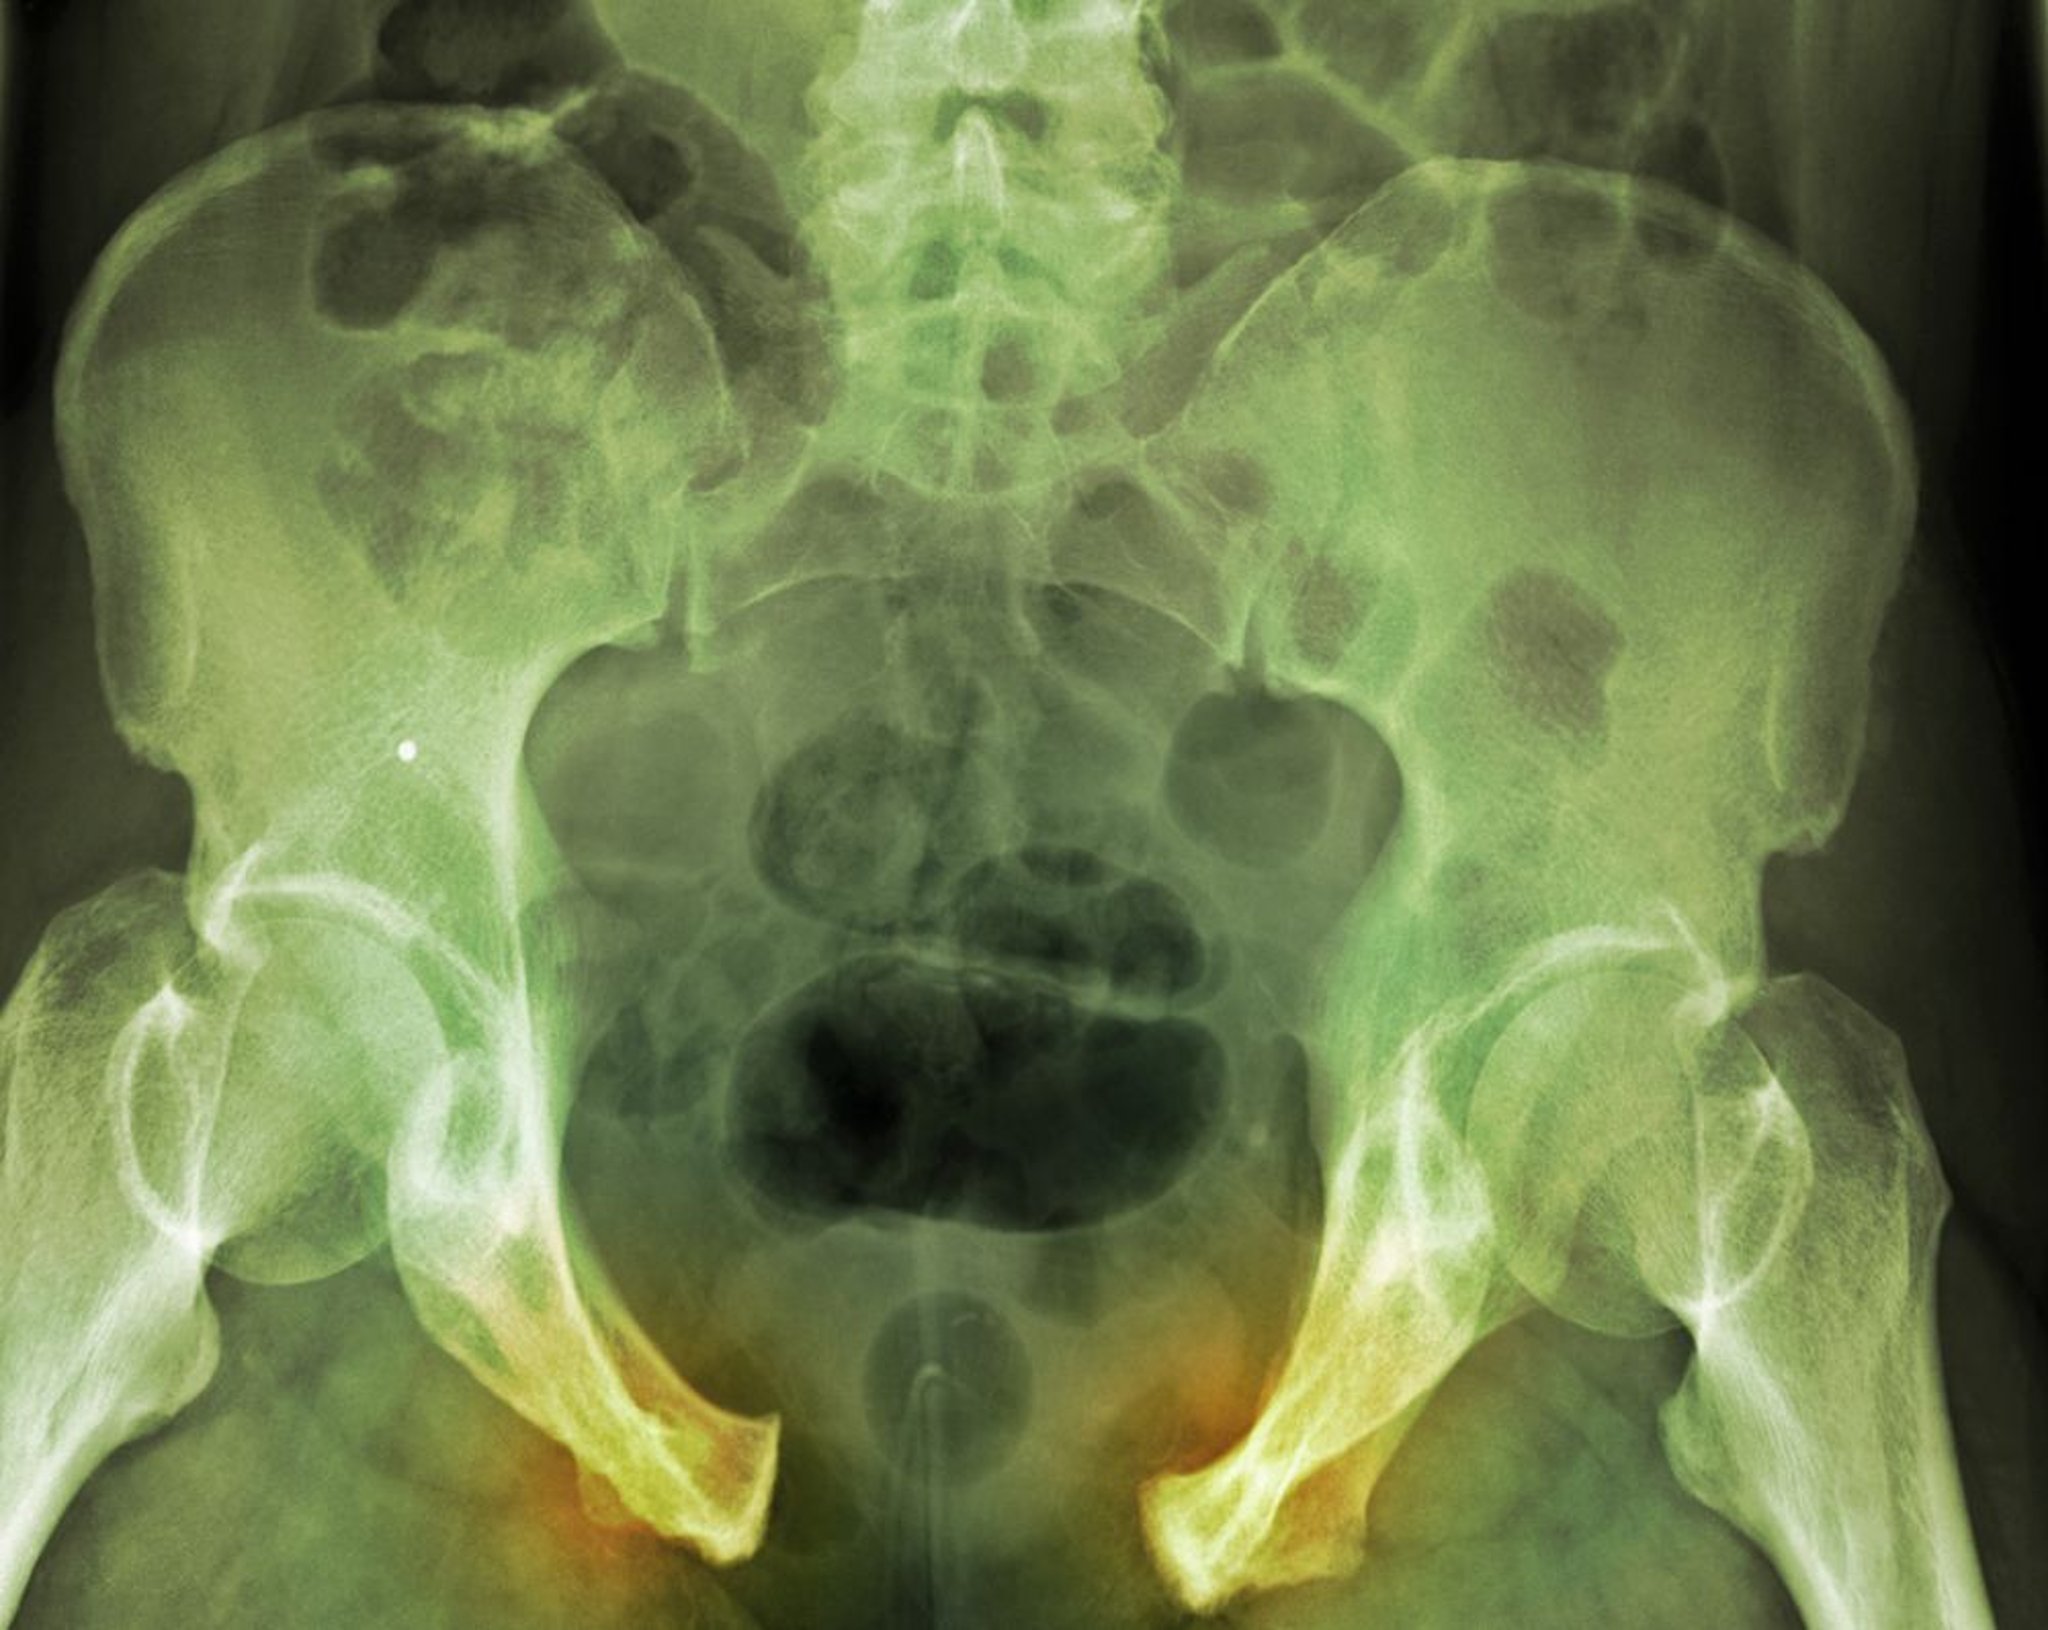

Fracture pelvienne

Dans cette lésion grave, la rupture de l'anneau pelvien est évidente du fait de la syndesmose des os pubiens largement séparés et des ligaments sacro-iliaques droits. Les lignes de fracture ne sont pas aussi évidentes.

DU CANE MEDICAL IMAGING LTD/SCIENCE PHOTO LIBRARY